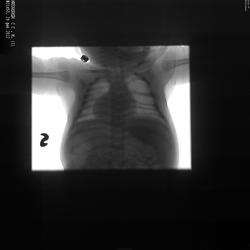

Аномалия позвоночника и ребер

Уважаемые коллеги, помогите разобраться с данной патологией. Ценно любое мнение. Снимок 3-месячного мальчика, сделан по поводу "Острый вирусный бронхит".Image preview